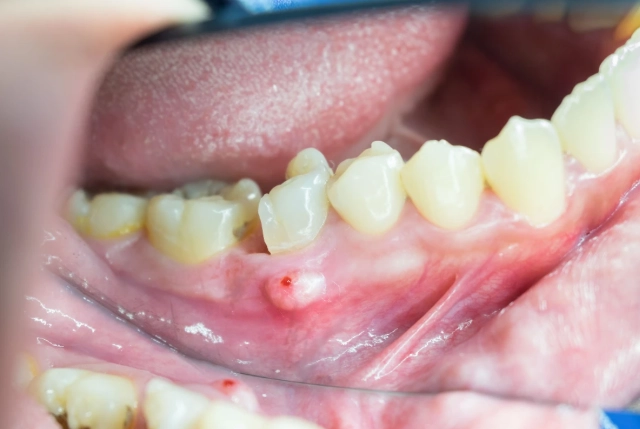

- Swelling in your gums near the tooth, which may feel tender or look like a small, red bump.

I had a patient, let's call him Mark, who felt a "small bump" on his gum for weeks. He ignored it because it didn't hurt much. When he finally came in, the infection had eroded a significant portion of his jawbone. Don't be like Mark. Swelling means the infection is spreading beyond the tooth.